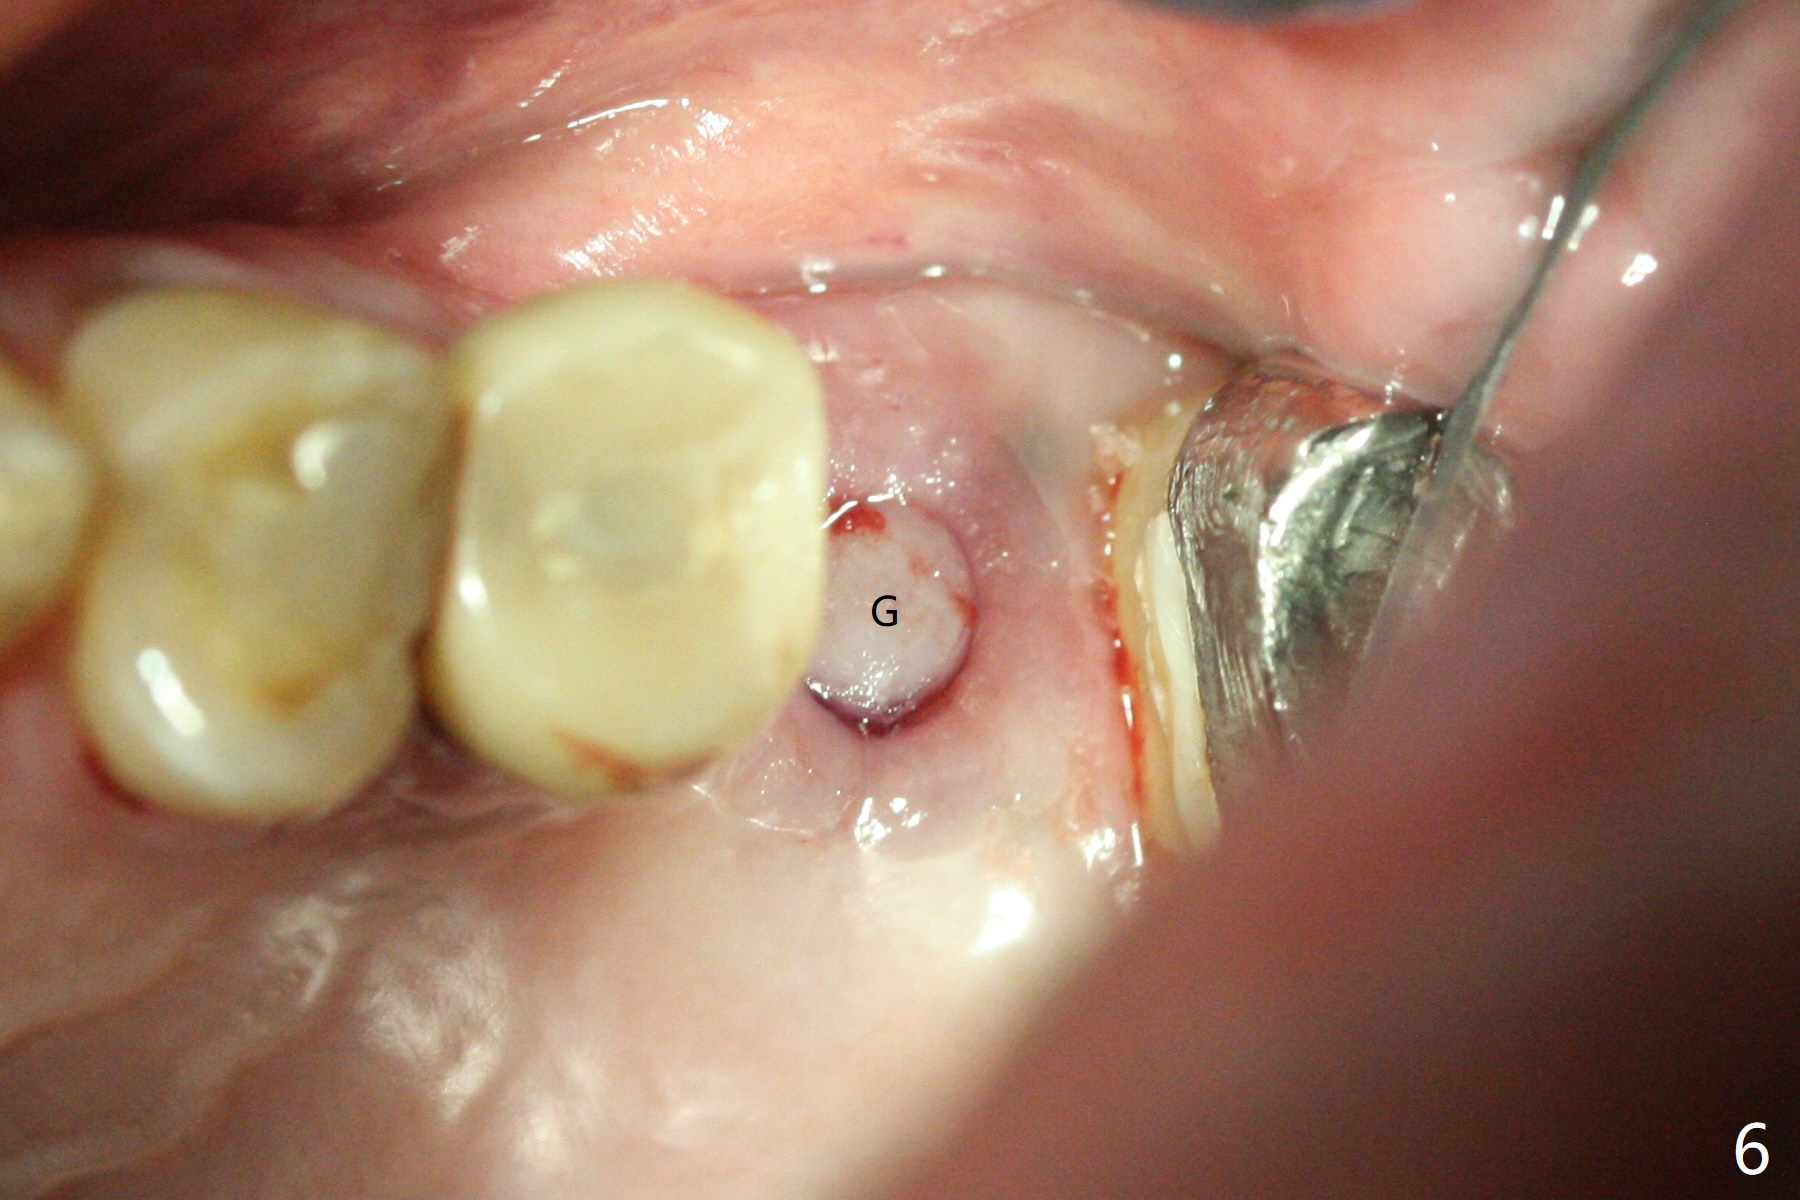

60岁男,左上6(牙根折裂严重骨质吸收)位点保存后6个月,回来植牙。术前CT显示骨质密度低,宽度足够,角化龈也宽,前后牙齿都有牙冠,制作导板麻烦,所以采纳徒手种植。使用4毫米活检打孔刀(Biopsy Punch)进入,简化手术,但是又怕开口不正,不敢用大号植体,术后CT发现钻洞偏颊侧。针对骨质密度低,使用1.2毫米钻头后(约8毫米),使用旋转式骨扩张器直至2.4/3.7毫米(图一(红虚线:原来骨质缺损)逐渐增加深度至11毫米),备洞几乎没有失去骨质,钻洞周围骨质密度谅必增高),取出最后一个扩大器后发现上颌窦底板破裂,放置粘性骨粉,使用4毫米报废植体做上颌窦提升,重复一次(图二,三),稳定性尚可。再次放置骨粉和PRF膜,使用正式植体提升(4.5x8毫米),临床上很难判断是否植体植入牙槽嵴之下(可能骨质疏松),只好拍摄CT(图四,五),好像正好牙槽嵴下,不过又植入骨粉一些(图七:*)。植体扭力~15Ncm,保险起见,放置愈合帽,表面放置少许骨粉以及打孔留下的牙龈(图六:G,之前一直泡在PRF上清液里),牙周胶水固定游离牙龈以及牙周敷料保护。术后6小时没有鼻出血。所以骨质缺损严重,植骨后,虽然缺损外形得到恢复,但是骨头质量,固定植体能力还不够。植牙时,需要适当改变手段,例如使用骨凿,提高骨质密度,而不是单纯使用钻头。术后病人恢复正常,没有疼痛,六天复诊,牙周敷料已经脱落,打孔的牙龈附着颊侧,部分骨粉暴露,但是看样子挺稳定,好像游离牙龈必须缝合。使用树脂敷料牢靠些。术后五周,伤口基本愈合,一处未愈合,与下面骨粉相通,用牙周探针稍微搅动,出血(图九)。擦干血迹,伤口还不错(图十)。术后2个月伤口好像正常愈合(图十一)。术后4.5个月根尖片显示6种植比5深,往后螺纹暴露可能性减少(图十二)。